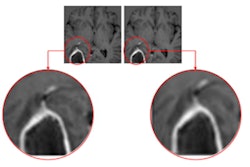

IB Neuro performs quantitative analysis of MRI dynamic susceptibility contrast (DSC) studies, a common perfusion MRI exam for evaluating brain tumors. Imaging Biometrics said that the software was included in the findings of a subcommittee on standardizing a DSC MRI protocol that was published in the journal Neuro-Oncology.

Imaging Biometrics believes that MRI-DSC imaging has been plagued by inconsistencies and suboptimal methods for acquiring and processing DSC-MRI scans. This results in mixed opinions regarding its usefulness. IB Neuro overcomes these limitations, according to the company.